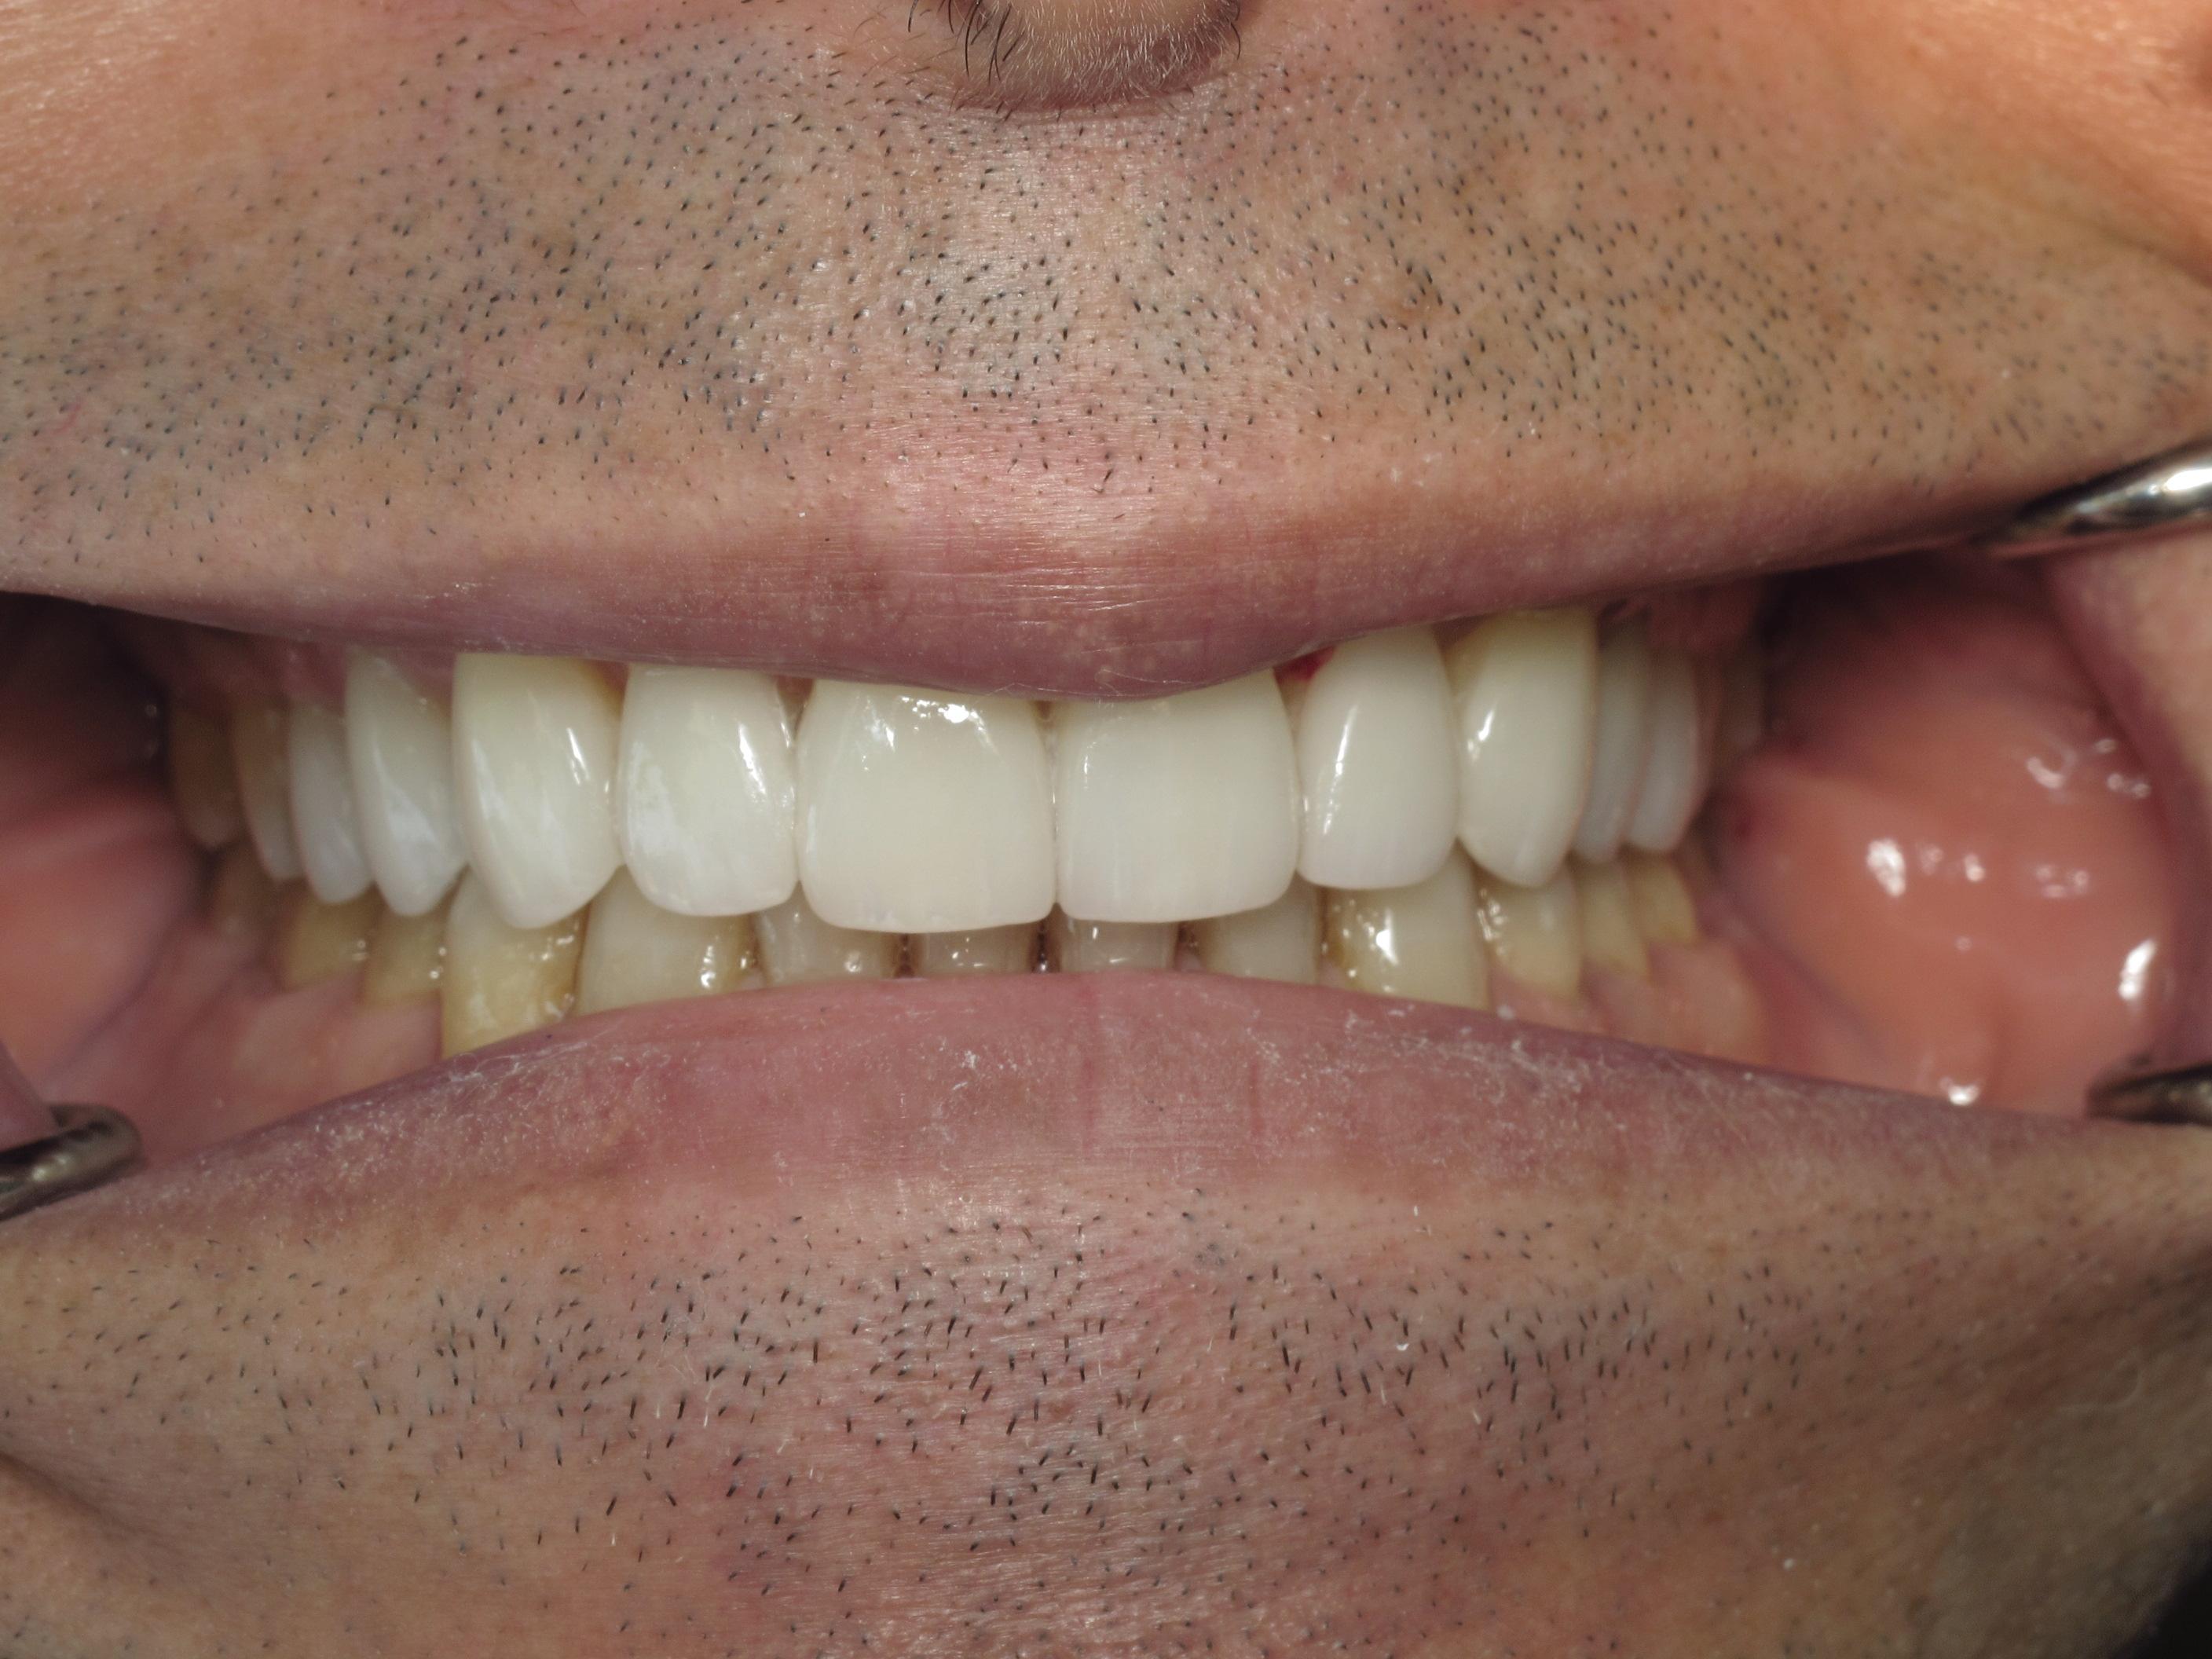

https://demo.discussdentistry.com/forums/topic/accident-victim-upper-arch-rehab/#post-26049 <![CDATA[Accident victim => Upper arch rehab]]> https://demo.discussdentistry.com/forums/topic/accident-victim-upper-arch-rehab/#post-26049 Tue, 30 Apr 2024 04:28:51 +0000 Amit Kumar The patient presents after falling in the bathroom and hitting his face on the countertop.  Previously, he had a PFM crown in the upper anterior.  He needed root canal therapy.

The patient is a stage performer (actor) and has appeared in some minor film roles, so he wanted to restore his teeth so that his smile would appear “white” on camera.

The patient’s lower teeth need attention and we will start the process once the patient’s finances have improved.

eMax material was used.  Pics were taken immediately after cementation.Before LeftBefore FrontBefore RightAfter FrontAfter LeftAfter Right